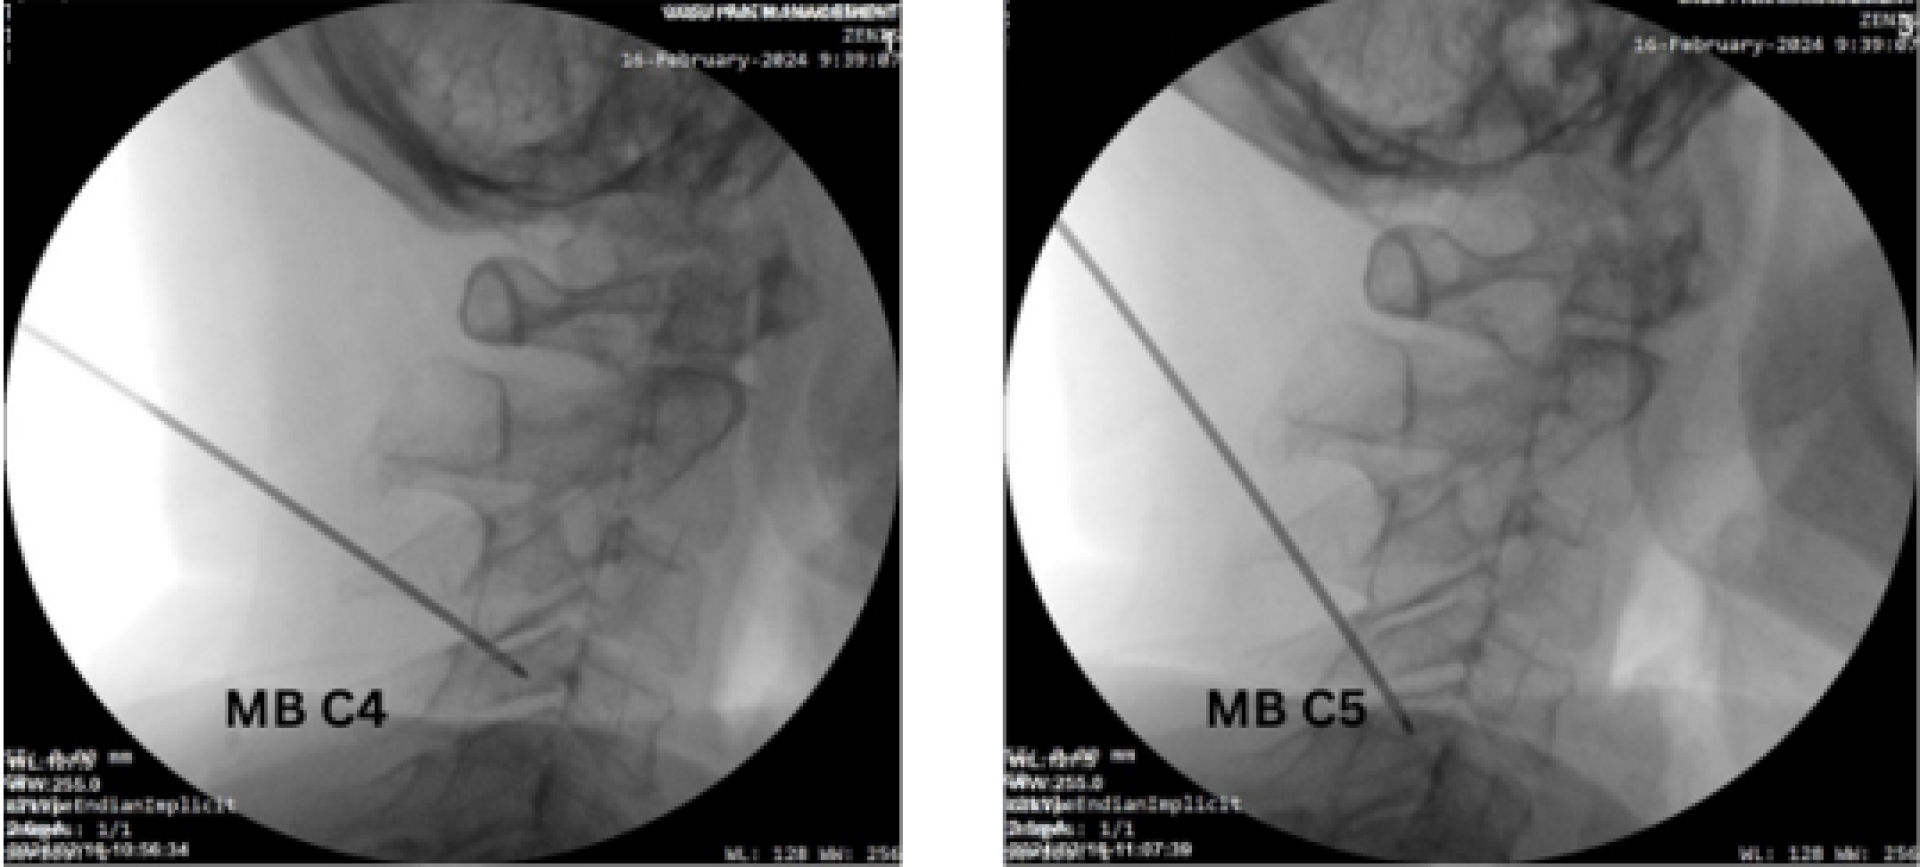

Cryoneurolysis is performed under ultrasound and fluoroscopic guidance to ensure accuracy and safety:

- Localization: The cervical medial branches are first identified using ultrasound for real-time visualization of soft tissues. Fluoroscopy is used concurrently to confirm vertebral level and needle placement.

- Probe Placement: A specialized cryoprobe is advanced to the target medial branch.

- Confirmation and Completion: Final imaging confirms treatment area before probe removal.